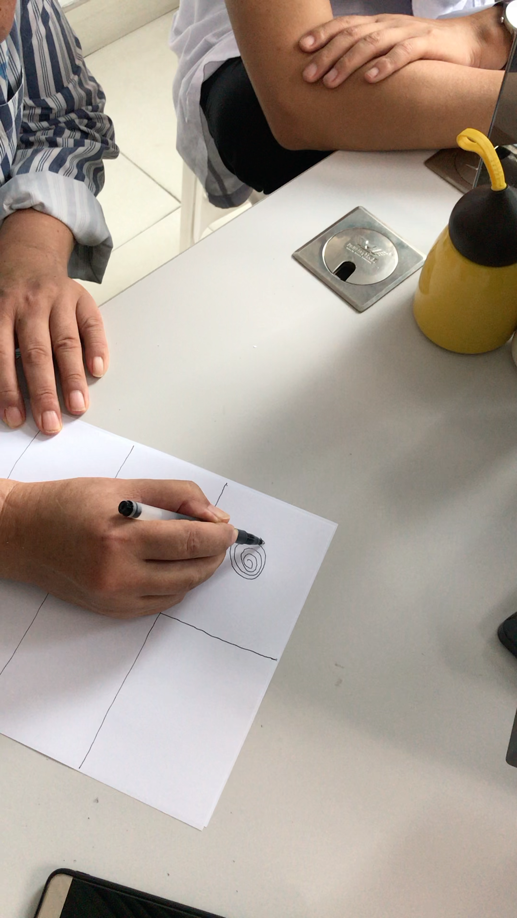

术后患者可以进行绘画和书写姓名